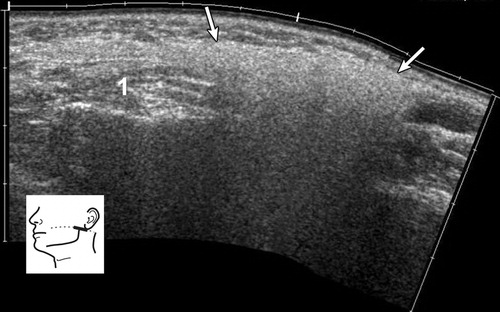

The parotid gland is located in the retromandibular fossa, in front of the ear and the sternocleidomastoid muscle.  The boundary between the superficial and deep parotid lobes is formed by a plane in which the facial nerve and its branches are located. The branches of the facial nerve are not visible on ultrasound. The deep parotid lobe can only be partially visualized on ultrasound.

The normal echogenicity of all major salivary glands, including the parotid gland, is generally homogeneous and varies between highly echogenic and mildly echogenic compared to adjacent muscles.

The echogenicity of the parotid gland depends on the amount of intraglandular fat tissue. Salivary glands with high fat content are more echogenic than surrounding muscles. The length of Stenson’s duct usually varies between 3 and 5 cm. During ultrasound examination, the non-dilated duct is generally invisible.